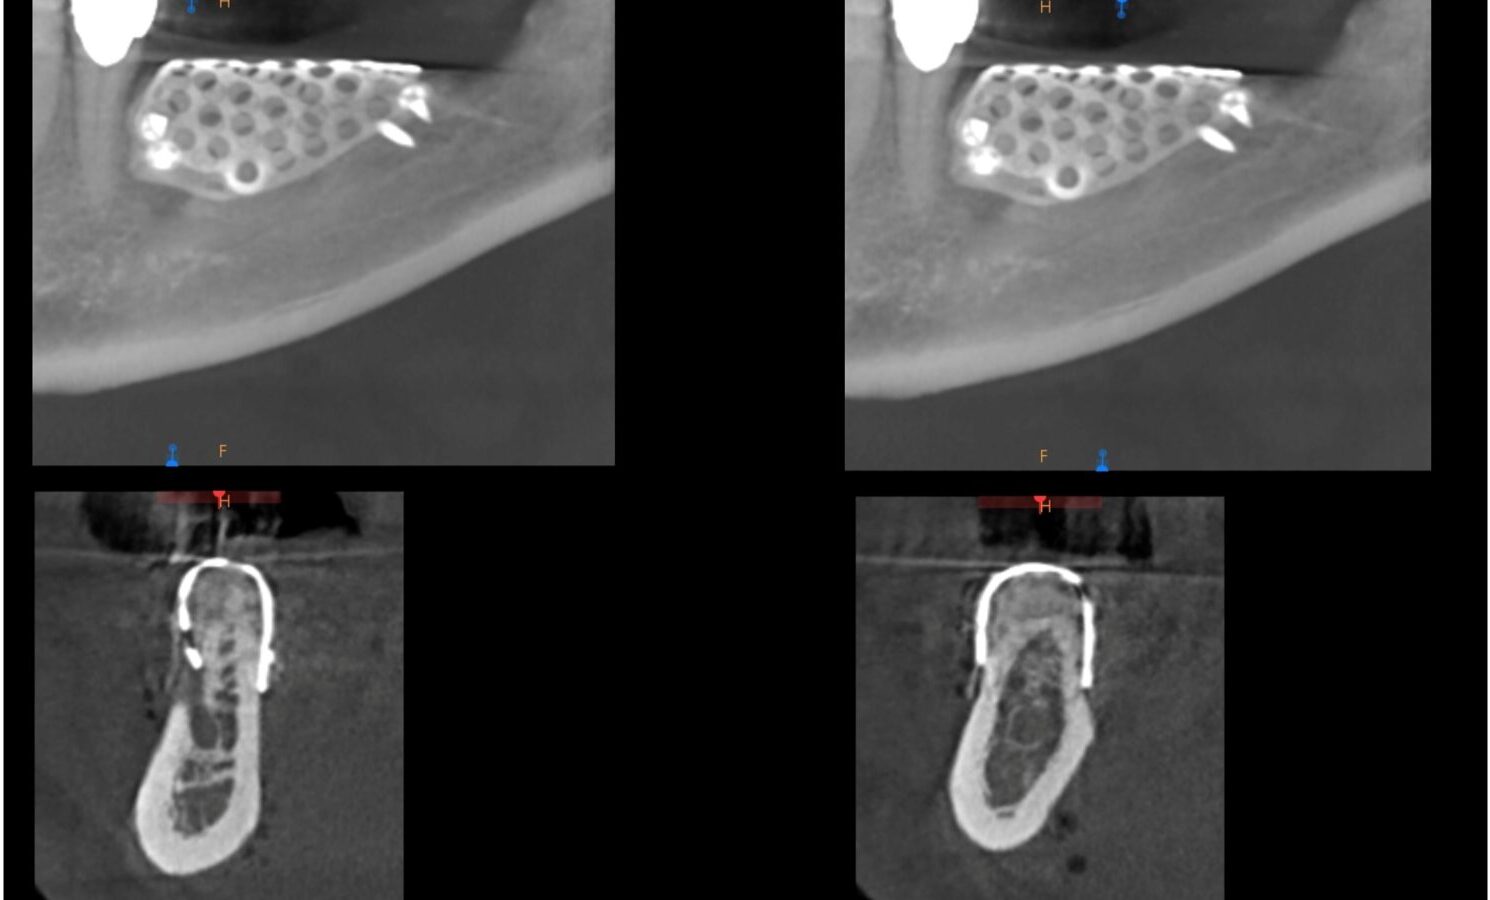

• INDAGINI DIAGNOSTICHE RADIOGRAFICHE

• PIANIFICAZIONE E TECNICHE CHIRURGICHE DEL RIALZO DI SENO MASCELLARE (MINI E GRANDE)

• PIANIFICAZIONE DEI CASI CLINICI DA OPERARE

• INTERVENTI DEI CORSISTI SU PAZIENTI